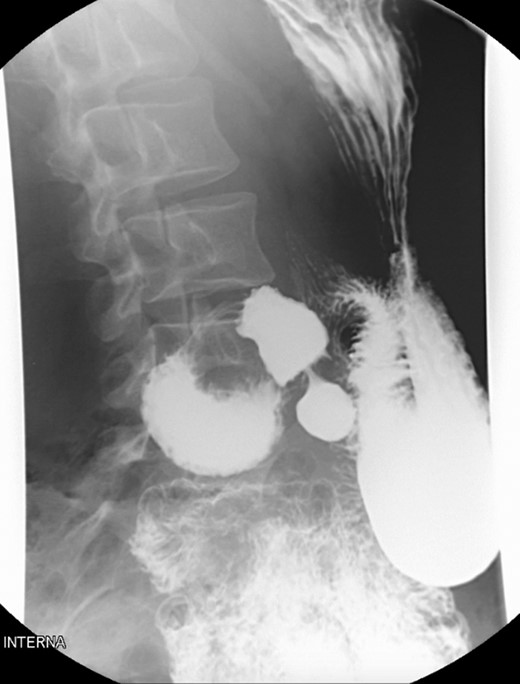

A 39-year-old Caucasian female patient presented to a General surgery outpatient clinic with complaints of epigastric pain, nausea, vomiting and weight loss for more than 5 years. The pain was worse after eating and with supine position. Vomiting was usually initiated 3–4 h after meals and consisted of undigested food. She had no significant prior medical history. On examination, the patient was extremely emaciated, with normal vital signs but with a distended abdomen and fullness over the epigastrium. She had already done an upper endoscopy that only showed gastric stasis. Abdominal ultrasound revealed a reduced angle between the AA and SMA (Fig. 1). An upper GI contrast study was requested, which revealed a distended stomach with delayed gastric emptying and lagging of contrast at the third portion of the duodenum (Fig. 2). Abdominal computed tomography (CT) scan was then performed. It demonstrated a severe distension of the stomach and proximal portions of the duodenum with constriction of the third part of the duodenum between the AA and SMA, with a reduced angle (11°) and shortened distance (4–5 mm) between these two arteries (Figs 3 and 4). These findings were suggestive of an aortomesenteric clamp. Hence, based on known findings, the diagnosis of Wilkie’s syndrome was established.

Contrasted intestinal series—distended stomach with delayed gastric emptying and reduced passage of contrast at the third portion of duodenum.